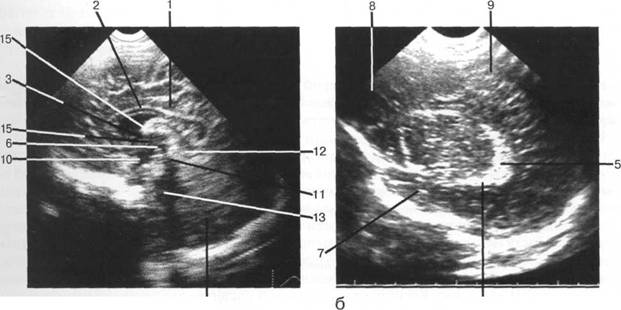

рога боковых желудочков; б - через структуры задней череп 13513u2010n 85;ой ямки.